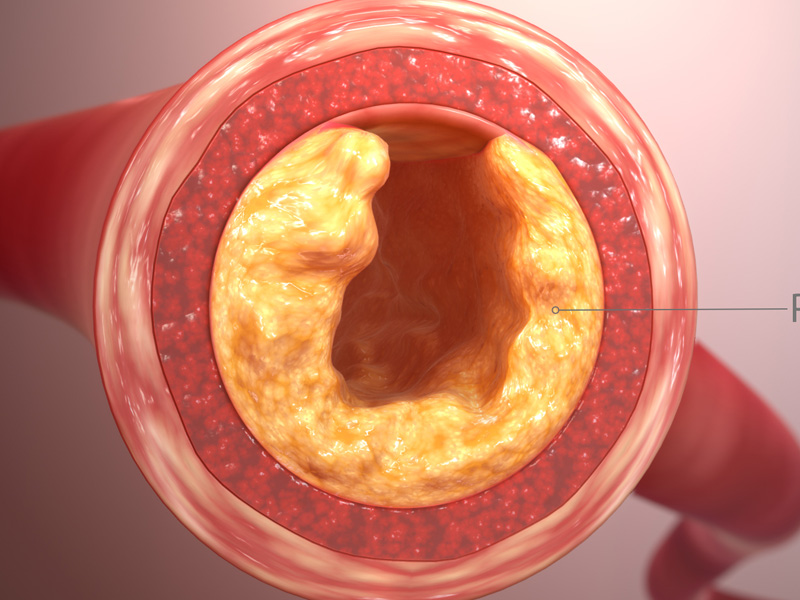

瀏覽:1988 體檢前這些事情不要做,否則檢查就白做了 |  瀏覽:48822 8 種降低膽固醇的食物,請常吃! |  瀏覽:4731 人為什麼那麼想吃鹹的? |